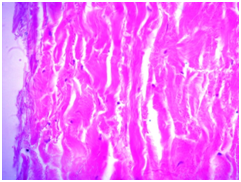

Lyophilized bovine pericardium - was presented as a narrow strip of connective tissue, mainly cell-free substance with no surface epithelium. Somewhere deep in the foundations were examined some fibroblasts with an elongated nucleus and clear cytoplasm. There were no signs of inflammation (Figure 1). When the preparations were stained with hematoxylin and eosin, it was easy to clearly distinguish the fibrous structure of the tissue.

During the immunohistochemical study, the structure of bovine pericardium was represented by loosely arranged bundles of unidirectional fibers. There was a weakly-positive reaction with VEGF and MMP-9, which indicates the slow occurring processes of angiogenesis and fibrosis. The negative reaction to collagen type-IV indicates a high degree of graft extensibility. Also, a negative response was observed with markers CD3 and CD20, suggesting that the LNT has passed multistage process which includes gamma irradiation, which allows to obtain a cell-free substance that contributes to inactivation of the infection.